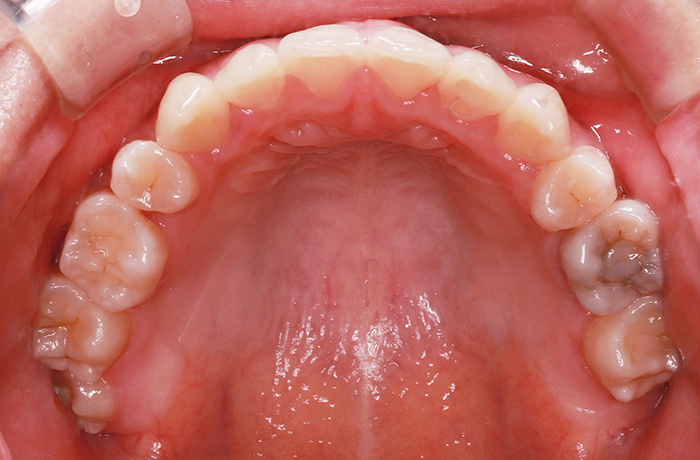

治療後

after

患者の症状 叢生、正中のずれ、上顎左右側切歯の口蓋側転位(交叉咬合)

治療方法 非抜歯で、マウスピース型カスタムメイド矯正歯科装置(インビザライン)による矯正

歯列弓を拡大することで非抜歯を可能にしました。

治療結果 側切歯の交叉咬合は解消、上下正中のずれも改善し咬み合わせが良くなりました。